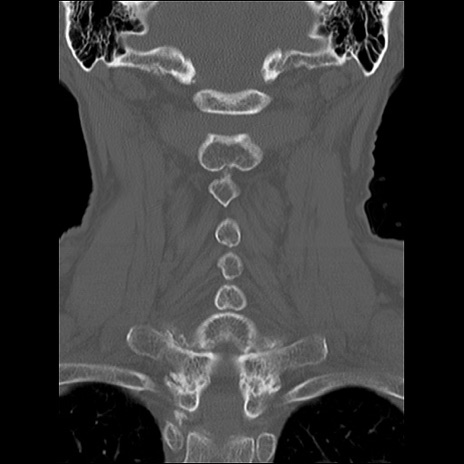

症例48 頚椎CT(冠状断像)

頚椎CT